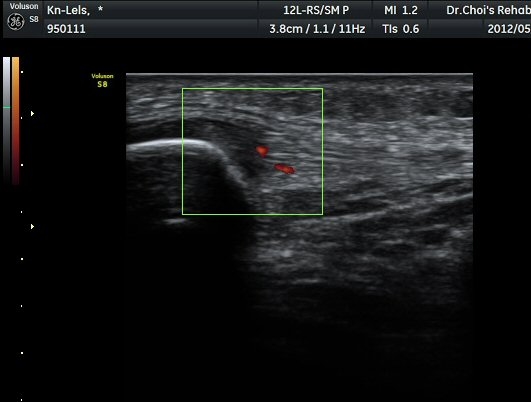

ÈûÁÙÀÇ ºñÈÄ´Â °ÇÃø(±×¸² 5)°ú ºñ±³ÇÏ¸é ¶Ñ·ÈÇϰí, ÆÄ¿öµµÇ÷¯°Ë»ç¿¡¼­ ÈûÁÙ³»¿¡

Ç÷·ùÁõ°¡µµ È®ÀδϵȴÙ(±×¸² 6, 7).